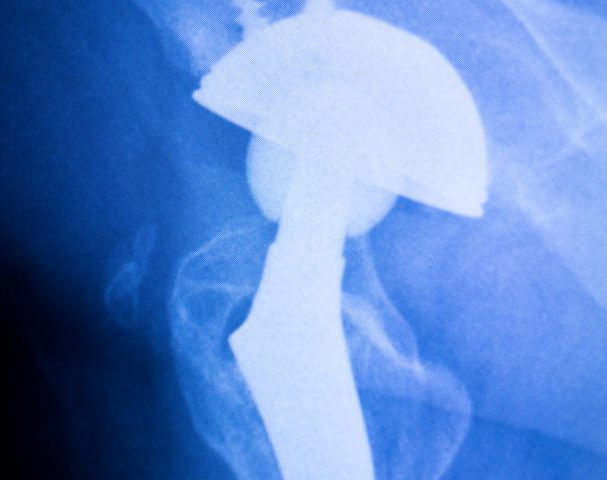

Hip Replacement Surgery

The hip joint is one the largest joints of the body that serves in the movement of the thigh, forward and backward. The hip joint also rotates when sitting, and with changes of direction while walking. The joint of the hip is where the ball of the thigh (femur) joins the pelvis at a socket…